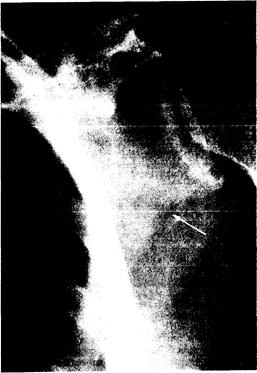

Рис. 337-3. Рентгенограмма ло­патки 58-летней женщины с фос­фатным диабетом.

Стрелка указывает на локализацию псевдоперелома, или зоны Лоозера.